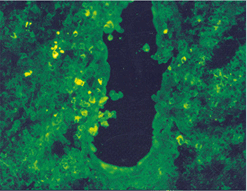

임상증상4

사진35 사진36 사진37

설명35 설명36 설명37